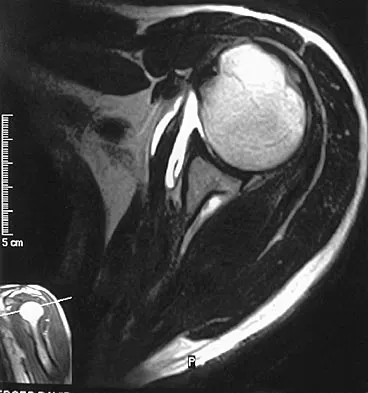

A 47-year-old male tennis player has pain in his nondominant shoulder that has failed to respond to 4 months of nonsurgical management. Examination reveals acromial tenderness and pain at the supraspinatus tendon insertion. He has a positive impingement sign, pain on forward elevation, and minimal cuff weakness. The MRI scans are shown in Figures 30a and 30b. To completely resolve his symptoms, treatment should consist of

Explanation

The MRI scans show a mesoacromion with tendonopathy of the supraspinatus. The history and physical findings indicate that the patient has a symptomatic os acromiale. Simple excision of the unstable os acromiale has not yielded consistently good results. Meticulous internal fixation using tension banding with cannulated screws and autologous bone grafting has shown good results for this problem. Hutchinson MR, Veenstra MA: Arthroscopic decompression of shoulder impingement secondary to os acromiale. Arthroscopy 1993;9:28-32.